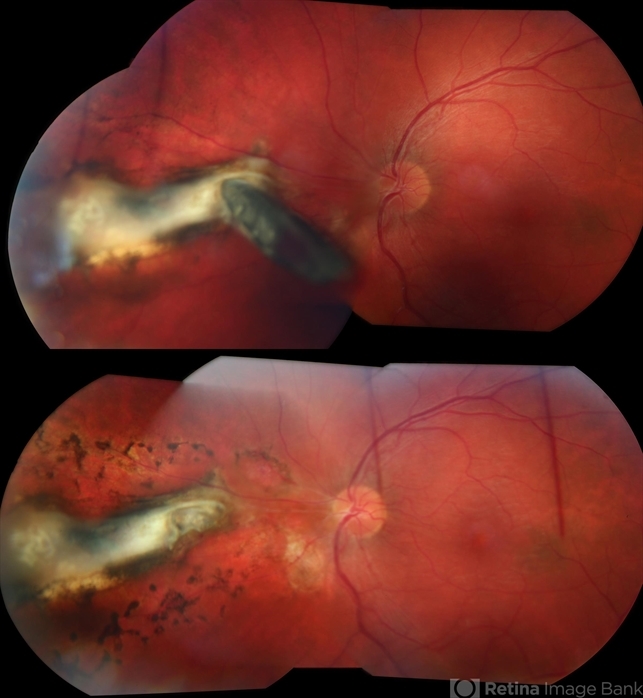

- Metallic Intraocular Foreign Body

- non metallic retained intraocular foreign body (RIOFB), encapsulated intraocular foreign body, penetrating trauma

- A 26-year-old gentleman presented with a metallic intraocular foreign body embedded in the nasal retina (above). Post-operative appearance two weeks after vitrectomy, foreign body removal, endolaser, and gas (below).